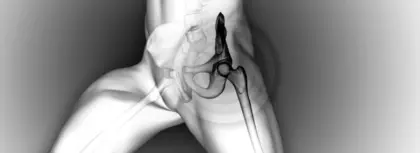

セラピストと膝関節内側の痛み

この非効率的な荷重と支持されていないシステムが速度と合わさったとき、私がめったに経験しないあることが現れました:膝関節内側の痛みです。